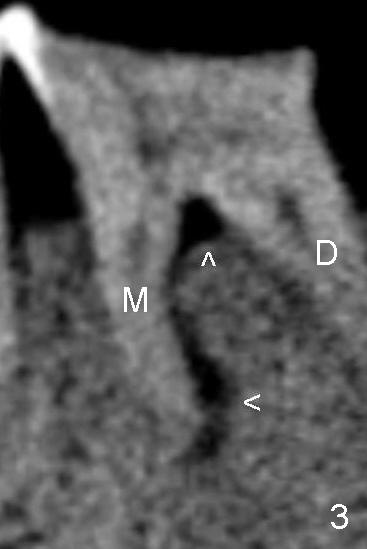

犹豫一阵子,最后决定采纳牙龈沟以及附加切口,翻瓣发现这个决策是英明(吹牛;至少视野好):右下第一磨牙整个近中根颊侧没有骨质覆盖,肉芽组织分布于根尖周围以及根分叉(图一箭头),与术前根尖片(图二)和根管治疗之前CT(图三:M:近中;D:远中)一致,心花怒放,一头栽入根尖切除术,心想病人有救了,尽管还背着黑锅:根尖炎加剧是根管治疗不妥所致。手术接近完成时,突然发现本人意料不到情况,您们猜是什么?提示多研究图一。不好意思,没有想考同学,不过想让大伙多多体验在美单枪匹马滋味(随时随刻作出判断,观察力要好)。不久见!